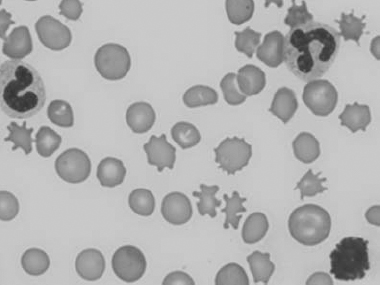

In the common domestic animals, mature erythrocytes are biconcave disks that are highly deformable, allowing them to travel through small capillaries and deliver oxygen to tissues (see Table 1.1). Erythrocyte aging and certain pathological conditions can cause RBCs to assume unusual shapes, which may result in increased rigidity. Rigid RBCs are susceptible to mechanical injury and are less effective in delivering oxygen. Exposure to stagnant environments (pooling of blood in a cavernous, hypoxic space), certain serum biochemical abnormalities, antibody-mediated membrane injury, and mechanical injury can alter the normal biconcave shape. Sometimes, RBC morphologic changes are associated with specific diseases or conditions, but the mechanism of the shape change is not clear (see Table 1.1 for diagrams of various types of RBC morphology).

See Figs 1.3–1.24 for pictures of various types of RBC morphology.

Figure 1.3 Canine blood film showing acanthocytes (also see color section).

Figure 1.10 Canine blood film showing echinocytes I (also see color section).

Figure 1.11 Canine blood film showing echinocytes III (also see color section).